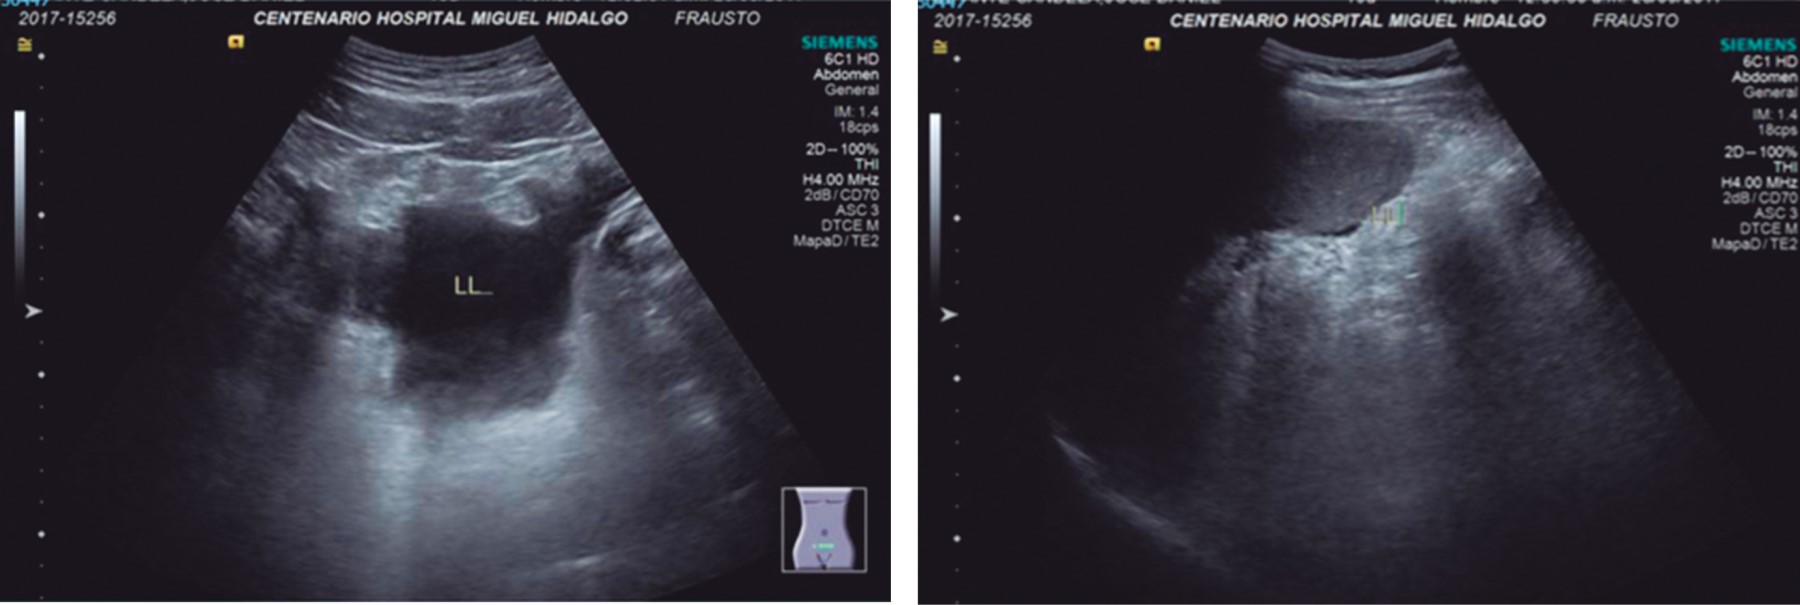

Ultrasonido abdominal: líquido libre subhepático, periesplénico y en recesos paravesicales (Figura 1).

Figura 1